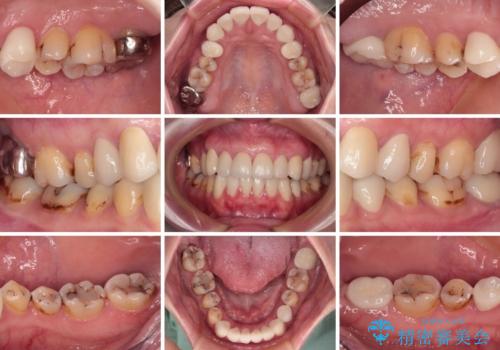

上顎前歯は歯肉退縮により歯根が露出していたため、事前に歯肉移植術により根面被覆を行い、その後にオールセラミッククラウンを装着することとしました。

歯肉移植術による根面被覆を行うかどうかは非常に悩まれていましたが、歯肉が覆われたことで長く見えていた歯の長さが整い、きれいな前歯の仕上がりとなりました。